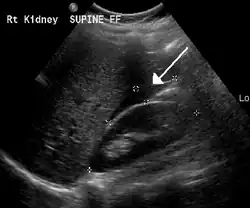

The use of ultrasound has become the standard of care when preparing a patient for paracentesis. Confirmation of an ascitic effusion reduces the risks associated with a dry or blind tap of the abdomen. Anatomic landmarks, such as the midline linea alba approach, were traditionally used as reference points for needle insertion. Phased array or curvilinear ultrasound transducers are typically used in the hospital and outpatient setting to identify ascites in the abdominal cavity. Fluid within the abdominal cavity appears hypoechoic or anechoic (black) on ultrasound. Morison's pouch (hepatorenal recess) is a common starting location in concordance with ultrasound FAST (focused assessment with sonography for trauma) exam. Fluid collection can occur in a number of different locations and may be difficult to find, especially if the patient only exhibits a small volume of ascites. Measurement of the amount of fluid within the abdominal cavity is not necessary or very successful. Identification of sufficient fluid within the abdominal cavity for fluid analysis or to achieve a therapeutic benefit is all that is required to proceed to paracentesis. Ultrasound guidance of the paracentesis can also be used as an additional safety measure to ensure the needle stays within the ascitic fluid and avoidance of important vessels within the abdominal cavity.[5]